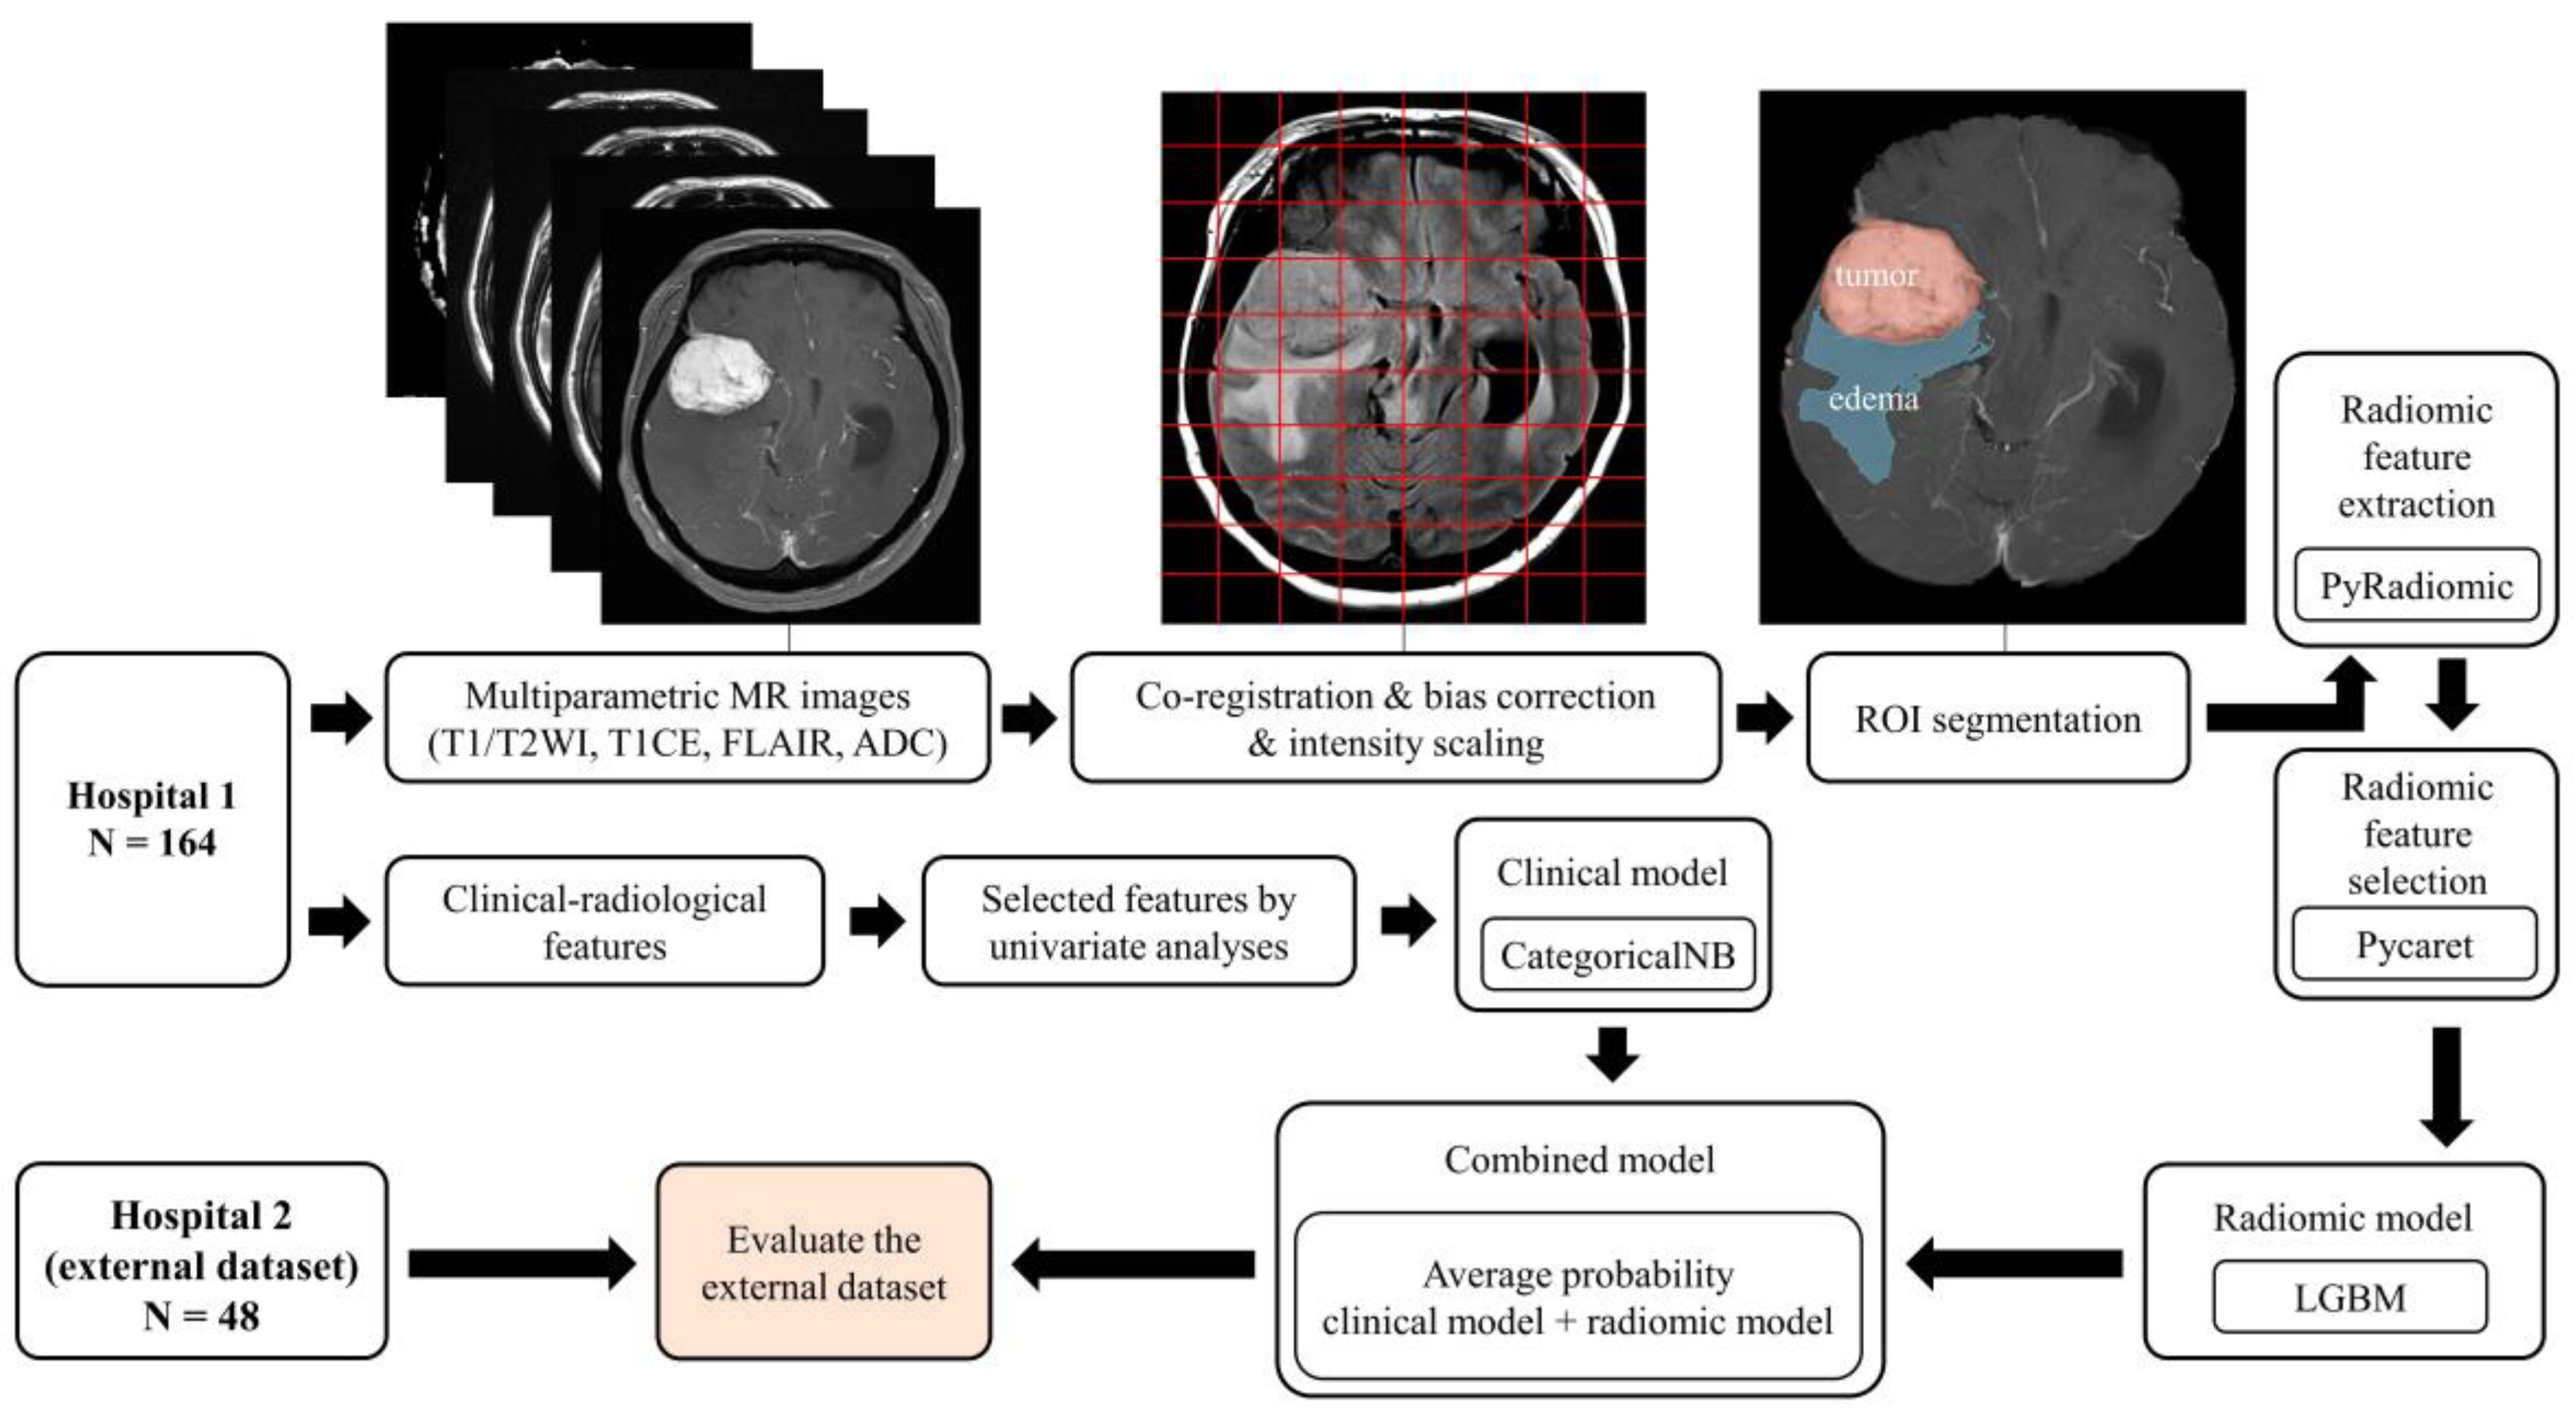

Typical Meningioma | Cohen Collection | Volumes | The。The Evolving Classification of Meningiomas: Integration of。Predicting Histologic Grade of Meningiomas Using a Combined。Meningiomas, Part II (Volume 170) (Handbook of Clinical Neurology, Volume 170) ハードカバー – 2020/8/14英語版 Michael W. McDermott MD (編集)※中古品のため、使用できれば良いという方のみのご購入をお待ちしております。角に少々イタミあり。中古品のため、多少のスレ、イタミ等ありますが、書き込みなく、とても良好な状態です。※商品状態の少々の見落としはご理解下さい。※値引交渉にはお答え致しません。※希少品の為、定価より高額の場合があります。※都合により発送方法を変更する場合があります。【佐川急便/日本郵便から佐川急便/日本郵便及びその逆等】※ビニールにて梱包し発送致しますが、保管、輸送によるイタミ等はご容赦下さい。※コメント不要、即購入にてご注文お願いします。。EANO guidelines for the diagnosis and treatment of。野口晴哉 口述 整体操法初等講座 全25冊。健康・医学専門雑誌コレクション。QB RB 2冊セット おまけ付き 看護師国家試験 2025年114回。【新品未使用】イヤーノート2026、内科専門医•総合内科専門医セット【バラ売可】。★8割復元!2024年度JBPOT復元。望診 自然療法 代替療法 医療 看護 大森英桜 日本CI協会 マクロビオティック。【裁断済み】メカニカル・リンク : オステオパシー・アプローチ。橋本